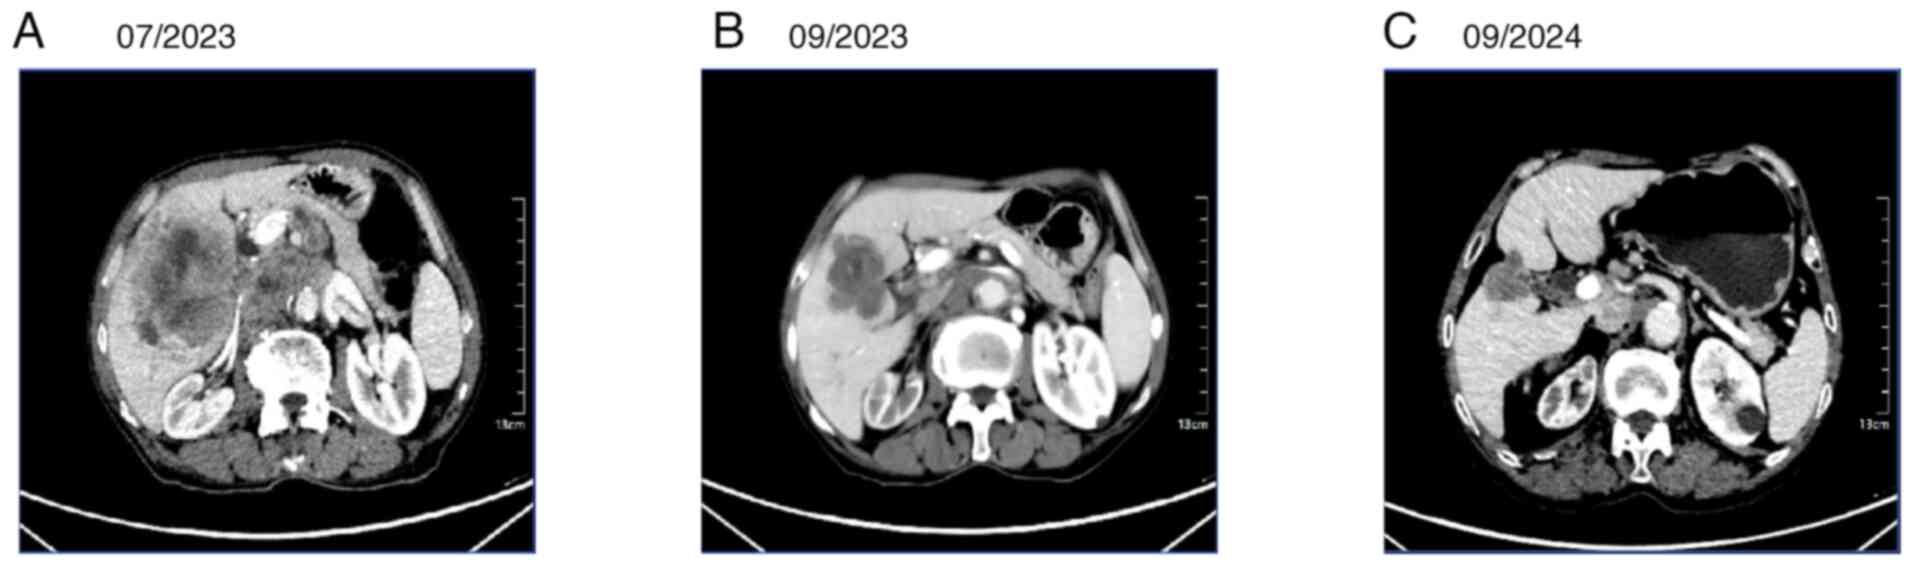

After multidisciplinary discussion, the patient was treated with envafolimab (200 mg subcutaneously once weekly) in combination with albumin-paclitaxel (200 mg on day 1 and 100 mg on day 5) plus cisplatin (30 mg on days 1–3). After two cycles (each cycle lasting 21 days), the efficacy evaluation indicated a partial response (PR) (Fig. 4A and B), which was sustained on subsequent evaluation (Fig. 4C). The tumor, initially shown on CT in July 2023 as multiple low-density nodules and a mass in the subcapsular region of the right lobe of the liver, with the largest measuring ~8.2×7.8 cm, had shrunk to 5.4×5.1 cm upon re-examination in September 2023, and further reduced to 3.3×3.0 cm when reviewed at Shaanxi Provincial Cancer Hospital in 2024. Following treatment, the patient's pain was significantly alleviated, physical strength was gradually recovered and mental status was improved. The various symptoms subsided, indicating a marked treatment effect. The multiple metastases were effectively controlled, the tumors significantly reduced in size, the tumor marker levels continued to decline (Fig. 5) and the patient's condition tended to be stable. With the improvement of physical condition, the patient's quality of life was also greatly enhanced, with normal mobility and diet. Telephone follow-up continued until December 2024 (a total of 18 months), during which time the patient maintained a sustained PR. Tumor marker levels continue to fall.

Figure 4.

Abdominal CT images before and after treatment. (A) Initial abdominal CT at diagnosis. (B) Abdominal CT after two cycles of treatment showing a reduction in tumor size. (C) More recent follow-up abdominal CT demonstrating a sustained partial response. CT, computed tomography.